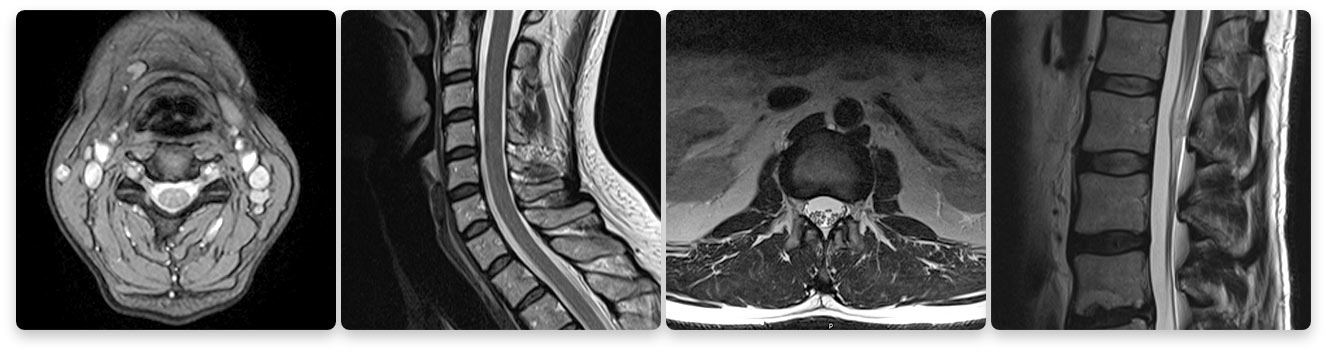

Texas Health Southlake's Imaging Department's 1.5T High Definition MRI Images

Seeing is believing. Do not compromise quality for a lower price. The images above compare a low strength machine to our 1.5T high-field machine. Two of the biggest factors that contribute to MRI image quality are strength of the magnet and skill of the technologist.

- 1.5T is the gold standard for a MRI in a clinical setting. DO NOT settle for less.

Beware of MRIs with lower magnet or tesla strength (Tesla is a measurement of magnetic field strength). The gold standard of MRI today is a 1.5T (T stands for tesla) strength MRI because it produces extremely clear images for a very accurate diagnosis. A lower-strength MRI produces images where the quality is much lower. You want to take care that you are not compromising your diagnosis when choosing an MRI.

1.5 tesla indicates the field-strength of the magnet used to obtain the images – the higher the field-strength, the more clear or detailed the images. A radiologist is looking to obtain the highest level of clarity for the most accurate diagnosis. Think of a spine injury. Let’s use, for example, a bulging disk. An MRI will show the anatomy of the vertebrae as well as the disks, spinal cord and the spaces between the vertebrae through which nerves pass. With such a complex image, your doctor will want the most clear, distinct picture so they can accurately assess the injury and make the proper diagnosis for treatment. The strength of the magnet is extremely important to achieve this clarity.

Lower strength means a less detailed image. The physician will have a harder time diagnosing the problem if he or she is looking at a low-quality image. These scans often take longer, making the patient more susceptible to movement resulting in reduced image quality. Lower image quality may lead to a longer wait time for the physician to read the scan or even misdiagnoses. Often prior to therapy, the entire scan may need to be redone. This costs you and your insurance company more money and may delay your diagnosis and treatment.

A true open MRI machine (one that is open on three sides) always has a tesla that is lower than 1.5. Patients sacrifice magnet power for a more open machine therefore they sacrifice image quality.